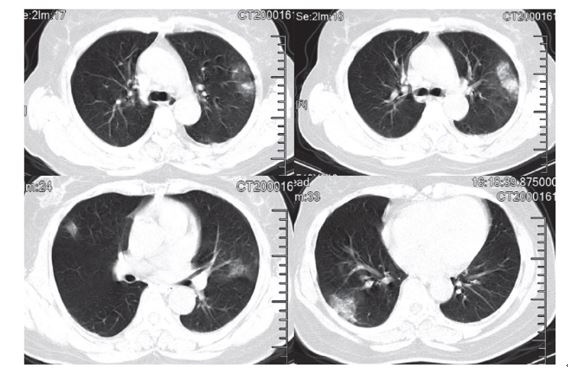

ÁÖ¿ä ÀÓ»ó ¾ç»óÀ¸·Î´Â °í¿­, ¸¶¸¥±âħ, ±ÙÀ°Åë, È£Èí°ï¶õ Áõ»óÀÌ ³ªÅ¸³ª¸ç, ÈäºÎ CT ÃÔ¿µ°á°ú Æó·Å ¼Ò°ßÀÌ ³ª¿Ô´Ù°í ¼Ò°³Çß´Ù. (Bilateral GGO, subsegmental consolidation)